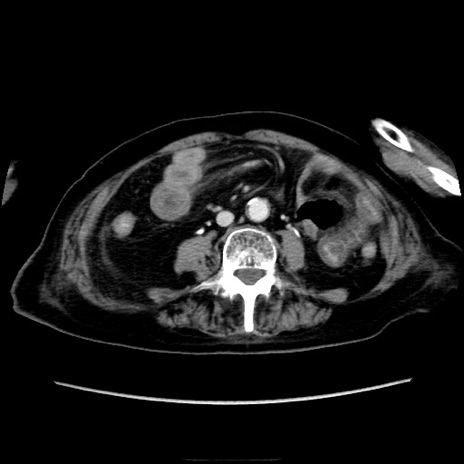

症例40(横断像)

【症例】90歳代女性

【主訴】腹痛・嘔吐

【現病歴】 食欲低下、嘔吐があり昨日他院受診。肺炎と診断され入院となる。入院後より腹部全体に圧痛あり。胃管留置され経過みていたが、症状持続するため、

当院転院となる。

【既往歴】胸椎圧迫骨折、胆石症

【身体所見】腹部:中央に激痛あり、圧痛あり、反跳痛不明

【データ】WBC 17100、CRP 18.82

横断像